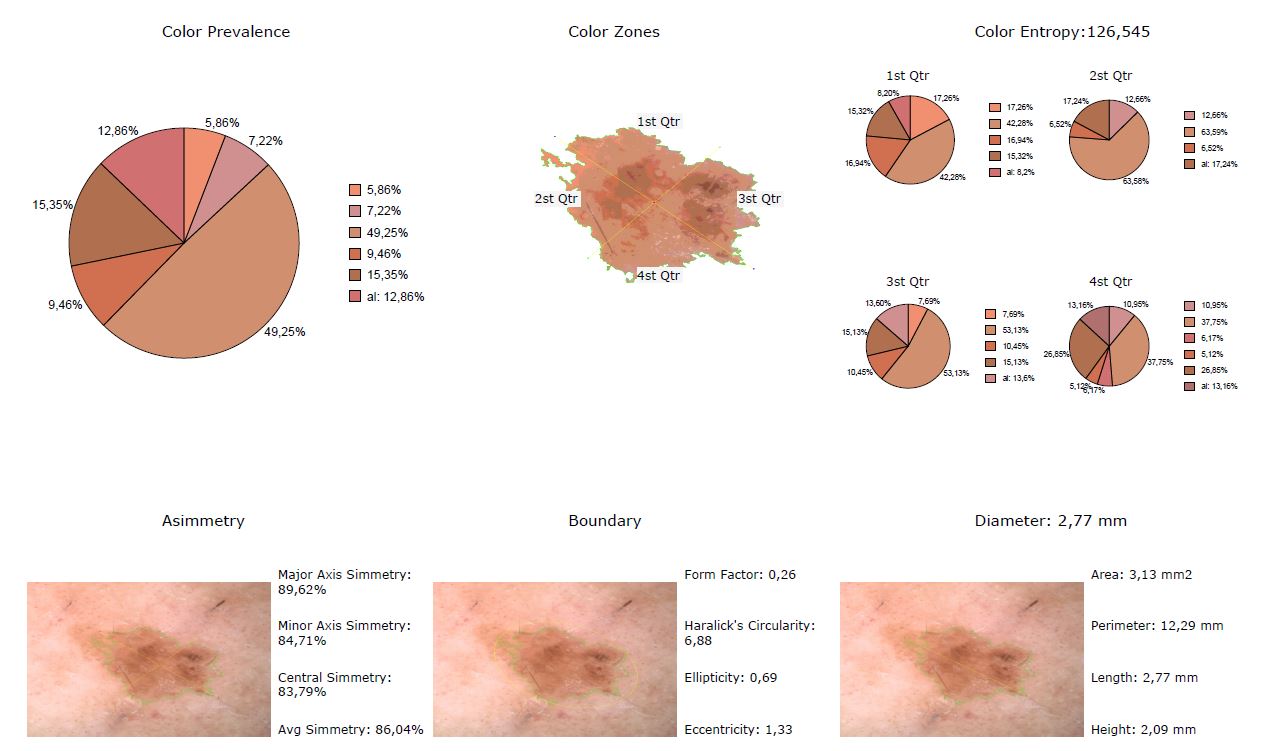

La funzione Segmentazione attiva l’analisi ABCDE su un’immagine di una lesione cutanea.

L’analisi ABCDE di IRSkin fornisce al medico informazioni quantitative riguardanti la morfologia e le caratteristiche pigmentarie della lesione cutanea.

Le funzioni di analisi ABCD, insieme alla possibilità di analizzare l’evoluzione di una lesione mediante la Body Map, forniscono informazioni quantitative e qualitative che possono aiutare il medico a migliorare la sua analisi ABCDE standard. Apparirà sullo schermo la schermata di analisi ABCD, insieme a i seguenti parametri numerici:

ASIMMETRIA:

Simmetria rispetto l’asse maggiore (percentuale di simmetria della pelle segmentata rispetto al suo asse maggiore di inerzia)

Simmetria rispetto l’asse minore (percentuale di simmetria della pelle segmentata rispetto al suo asse minore di inerzia)

Simmetria rispetto al centro (percentuale di simmetria della pelle segmentata rispetto al suo baricentro)

Simmetria media (media delle tre simmetrie precedenti)PARAMETRI DEL CONTORNO

Fattore di forma (quantità numerica che misura la complessità del contorno di una forma rispetto alla sua area: è proporzionale al rapporto tra l’Area della lesione cutanea e il quadrato del suo Perimetro. I piccoli valori del Fattore di forma indicano che la lesione ha un confine articolato)

Circolarità di Haralick (quantità statistica che misura la somiglianza di una forma con un cerchio) I grandi valori della circolarità dell’Haralick indicano che la lesione ha un’elevata circolarità

Ellitticità (quantità numerica che misura la somiglianza di una forma con la sua ellisse inerziale) I grandi valori di ellitticità indicano che la lesione è simile alla sua ellisse inerziale)

Eccentricità (quantità numerica che misura il rapporto tra gli assi inerziali di una forma: valori elevati di Eccentricità indicano una estesa lesione cutanea)COLORE:

Colore dominante (grafico che indica la distribuzione dei colori prevalenti della lesione cutanea)

Visualizzazione zone di colore(dei colori prevalenti della lesione cutanea e dei suoi assi inerziali)

Colore Entropia (quantità statistica, definita dal Team IRSkin, che misura le variazioni di colore della lesione cutanea tra i suoi quattro quarti)PARAMETRI DIMENSIONALI (espressi in millimetri):

Diametro (distanza massima tra due punti di una lesione cutanea)

Area (misura dell’area coperta dalla lesione cutanea)

Perimetro (misura della lunghezza del confine della lesione cutanea)

Lunghezzaì(misura della lunghezza dell’asse maggiore della lesione cutanea)

Altezza (misura della lunghezza dell’asse minore della lesione cutanea)